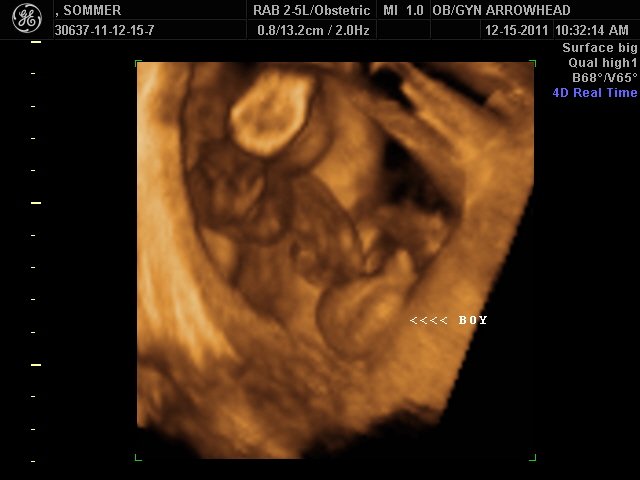

We offer complimentary 3D/4D Ultrasounds to all our OB patients around 30 weeks! The following photos are some examples of our work, shown with permission from our patients.